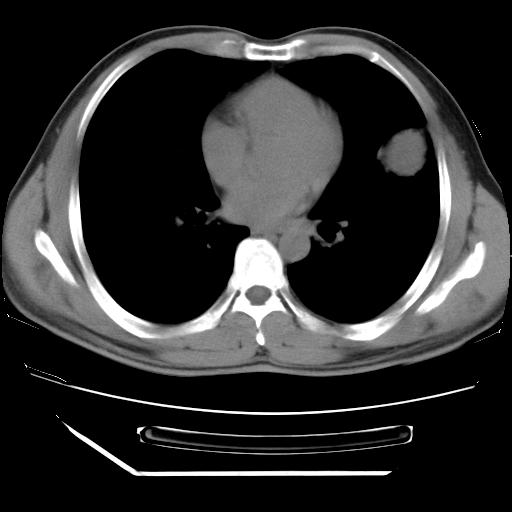

男,38岁,于2009年8月9日晚突发左侧胸痛,今x线提示左下肺阴影,为了明显确诊断,行ct检查,

血常规:嗜酸性细胞增高,单核细胞增高。

纵膈窗

病灶发生在下叶,密度均匀,边缘模糊、毛糙,周围血管纹理增强扭曲改变,靠近胸膜处病灶胸膜反应明显。

支持考虑---球形肺炎。

左肺舌叶病变。主体病灶呈类圆形中心密度低,成液化趋势周边班片影分布

考虑肺脓肿

虽然实验室检查支持炎性病变,且病变内有坏死改变(中央呈大片状低密度影),但仍不能掉以轻心,鳞癌也可以有这种影像改变。